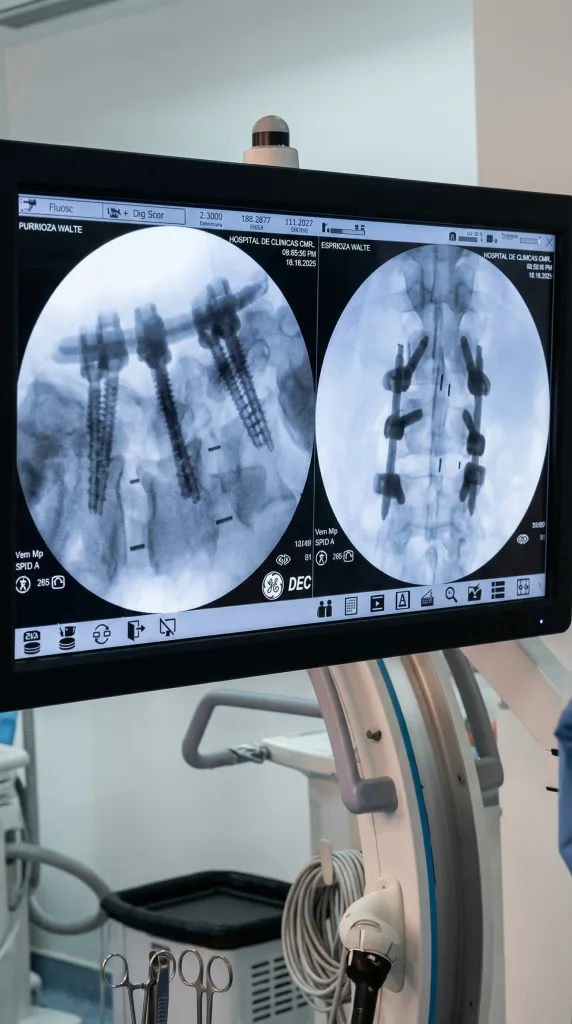

Cirugía Mínimamente Invasiva con fusión lumbar transforaminal “transforaminal lumbar interbody fusion”(TLIF).

La TLIF es un procedimiento avanzado mínimamente invasivo de fusión vertebral, en el que las vértebras se estabilizan para aliviar la presión sobre los nervios y el dolor de espalda. Se trata de una alternativa mínimamente invasiva a los antiguos métodos de fusión vertebral más invasivos, que eran más dolorosos y requerían períodos de recuperación más largos. La TLIF se realiza a través de dos incisiones muy pequeñas en la espalda, por lo que los pacientes experimentan menos dolor, tiempos de recuperación más cortos y menos complicaciones quirúrgicas.

La fusión lumbar transforaminal (TLIF ) es una opción. Este procedimiento quirúrgico se realiza a través de una incisión en el centro de la espalda. Consiste en eliminar la presión sobre los nervios de la espalda y también estabiliza la columna vertebral realizando una fusión con tornillos y un pequeño «espaciador» que se coloca en el espacio discal.

La fusión espinal es necesaria cuando dos o más vértebras están comprimidas, ya sea por una enfermedad degenerativa de la columna, como una hernia discal, espondilolistesis o artritis, o por una lesión. La pérdida del espacio y la amortiguación adecuados entre las vértebras puede provocar un dolor de espalda y piernas debilitante que sólo puede resolverse mediante cirugía. La cirugía de fusión vertebral restablece el espacio entre las vértebras y fusiona los huesos en su lugar utilizando instrumentación (varillas y tornillos) para mantenerlos en posición e injertos óseos (una pasta de material óseo que se endurece con el tiempo) para impedir permanentemente que las vértebras se muevan.

Se extrae un disco intervertebral degenerado y se puede realizar una fusión intercorporal insertando un espaciador lleno de injerto óseo o sustituto óseo en el espacio del disco. Luego, el cirujano puede realizar todo el procedimiento de TLIF utilizando un microscopio a través de un sitio de incisión más pequeño.

Una vez realizada la fusión en el espacio discal, el siguiente paso es estabilizar el segmento de la columna mediante la inserción de un tornillo a través de pequeñas incisiones cutáneas (fijación percutánea con tornillos pediculares).